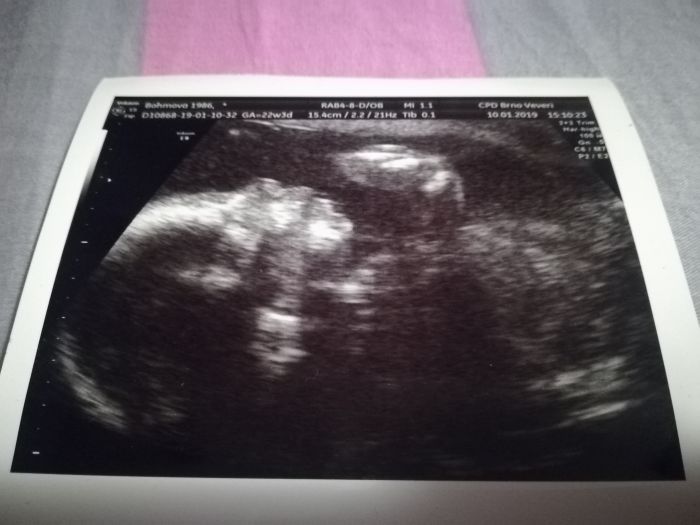

Ahoj holky, ve čtvrtek na kontrole dopadlo vše dobře. Vzhledem k předchozímu potratu kvůli vade kosti, sem byla u doktorky dlouho. Na ultrazvuku se koukala jestli má malej všechny kosti jak mají být. A vše dopadlo dobře ?. Malej se nechtěl otočit tak sem asi 20min. chodila po ordinaci ?. Na cukrovku jdu od 29.1. Takže se objednám až na únor. Mám aji fotku